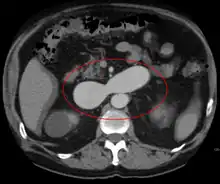

AVMs are diagnosed primarily by the following imaging methods:[12]

- Computerized tomography (CT) scan is a noninvasive X-ray to view the anatomical structures within the brain to detect blood in or around the brain. A newer technology called CT angiography involves the injection of contrast into the blood stream to view the arteries of the brain. This type of test provides the best pictures of blood vessels through angiography and soft tissues through CT.

- Magnetic resonance imaging (MRI) scan is a noninvasive test, which uses a magnetic field and radio-frequency waves to give a detailed view of the soft tissues of the brain.

- Magnetic resonance angiography (MRA) – scans created using magnetic resonance imaging to specifically image the blood vessels and structures of the brain. A magnetic resonance angiogram can be an invasive procedure, involving the introduction of contrast dyes (e.g., gadolinium MR contrast agents) into the vasculature (circulatory system) of a patient using a catheter inserted into an artery and passed through the blood vessels to the brain. Once the catheter is in place, the contrast dye is injected into the bloodstream and the MR images are taken. Additionally or alternatively, flow-dependent or other contrast-free magnetic resonance imaging techniques can be used to determine the location and other properties of the vasculature.

AVMs can occur in various parts of the body: